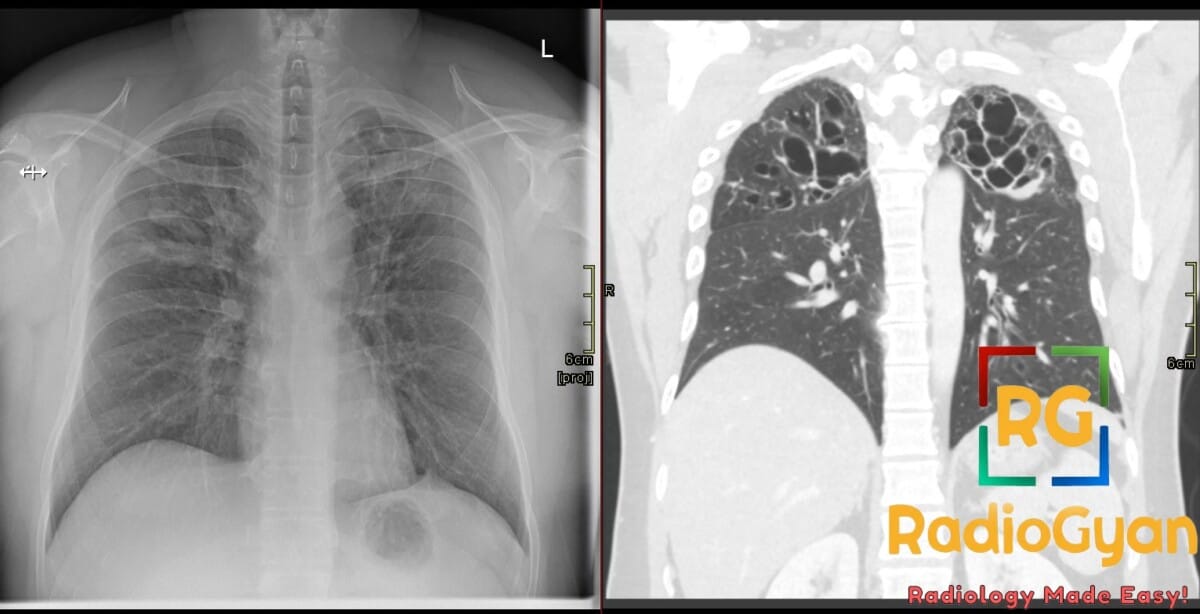

Gloved finger sign is caused by mucoid impaction within dilated bronchi, appearing as branching, finger-like tubular opacities radiating from the hilum on chest radiography or CT. This imaging finding is commonly associated with conditions that cause airway obstruction or bronchial dilation, including allergic bronchopulmonary aspergillosis (ABPA), bronchial atresia, bronchiectasis, cystic fibrosis, broncholithiasis, bronchial tuberculosis, and foreign body aspiration. Clinically, these conditions involve mucus plugging due to impaired clearance or direct bronchial obstruction.

The sign is named “gloved finger” because the radiologic branching, finger-like opacities resemble the shape of a finger of a glove; the mucus filling dilated bronchi project outward in a pattern similar to glove fingers extending from the hand.

The sign develops due to accumulation of thick, inspissated mucus within bronchial lumens that are dilated either congenitally or secondary to inflammation and obstruction. The mucus-filled bronchi appear as tubular opacities with branching morphology on imaging. The bronchial dilation (bronchiolectasis or bronchiectasis) and the mucus impaction cause the characteristic appearance. The obstruction leads to mucus stasis and recurrent infection/inflammation, perpetuating airway dilation and mucus retention.